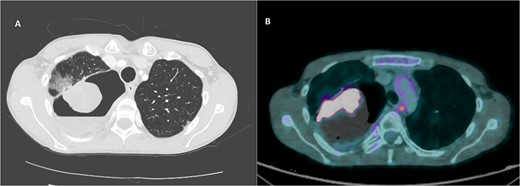

Ultimately, the patient had a right thoracotomy en bloc wedge resection of the right upper and lower lobe (Fig. 3A). The tumor was well-encapsulated and was 10.8 × 9.8 × 7.7 cm in size (Fig. 3B).

En bloc wedge resection of the right upper and lower lobe (A). The right upper lobe mass was a well-encapsulated tumor and measured 10.8 × 9.8 × 7.7 cm (B).